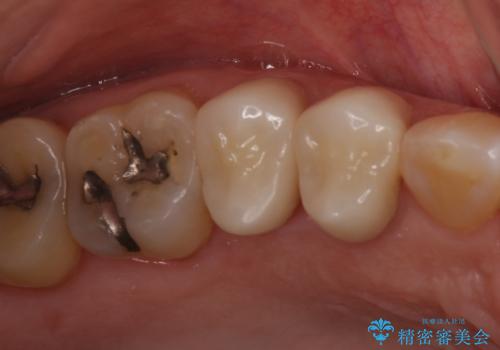

- 前歯のすきっぱを主訴にご来院された患者様です。他院でつめものやラミネートべニア(前歯の表面のみセラミックを貼り付ける)を行っていましたが、頻繁に外れることに悩まれており、クラウン(歯全体をセラミックがつつむ)をご希望されました。また、奥歯に大きな虫歯があり、歯が割れていたため、奥歯の治療も併せて行いました。

右上の歯に関しても、大きな虫歯があったため、前歯の経過観察の間に治療を行いました。